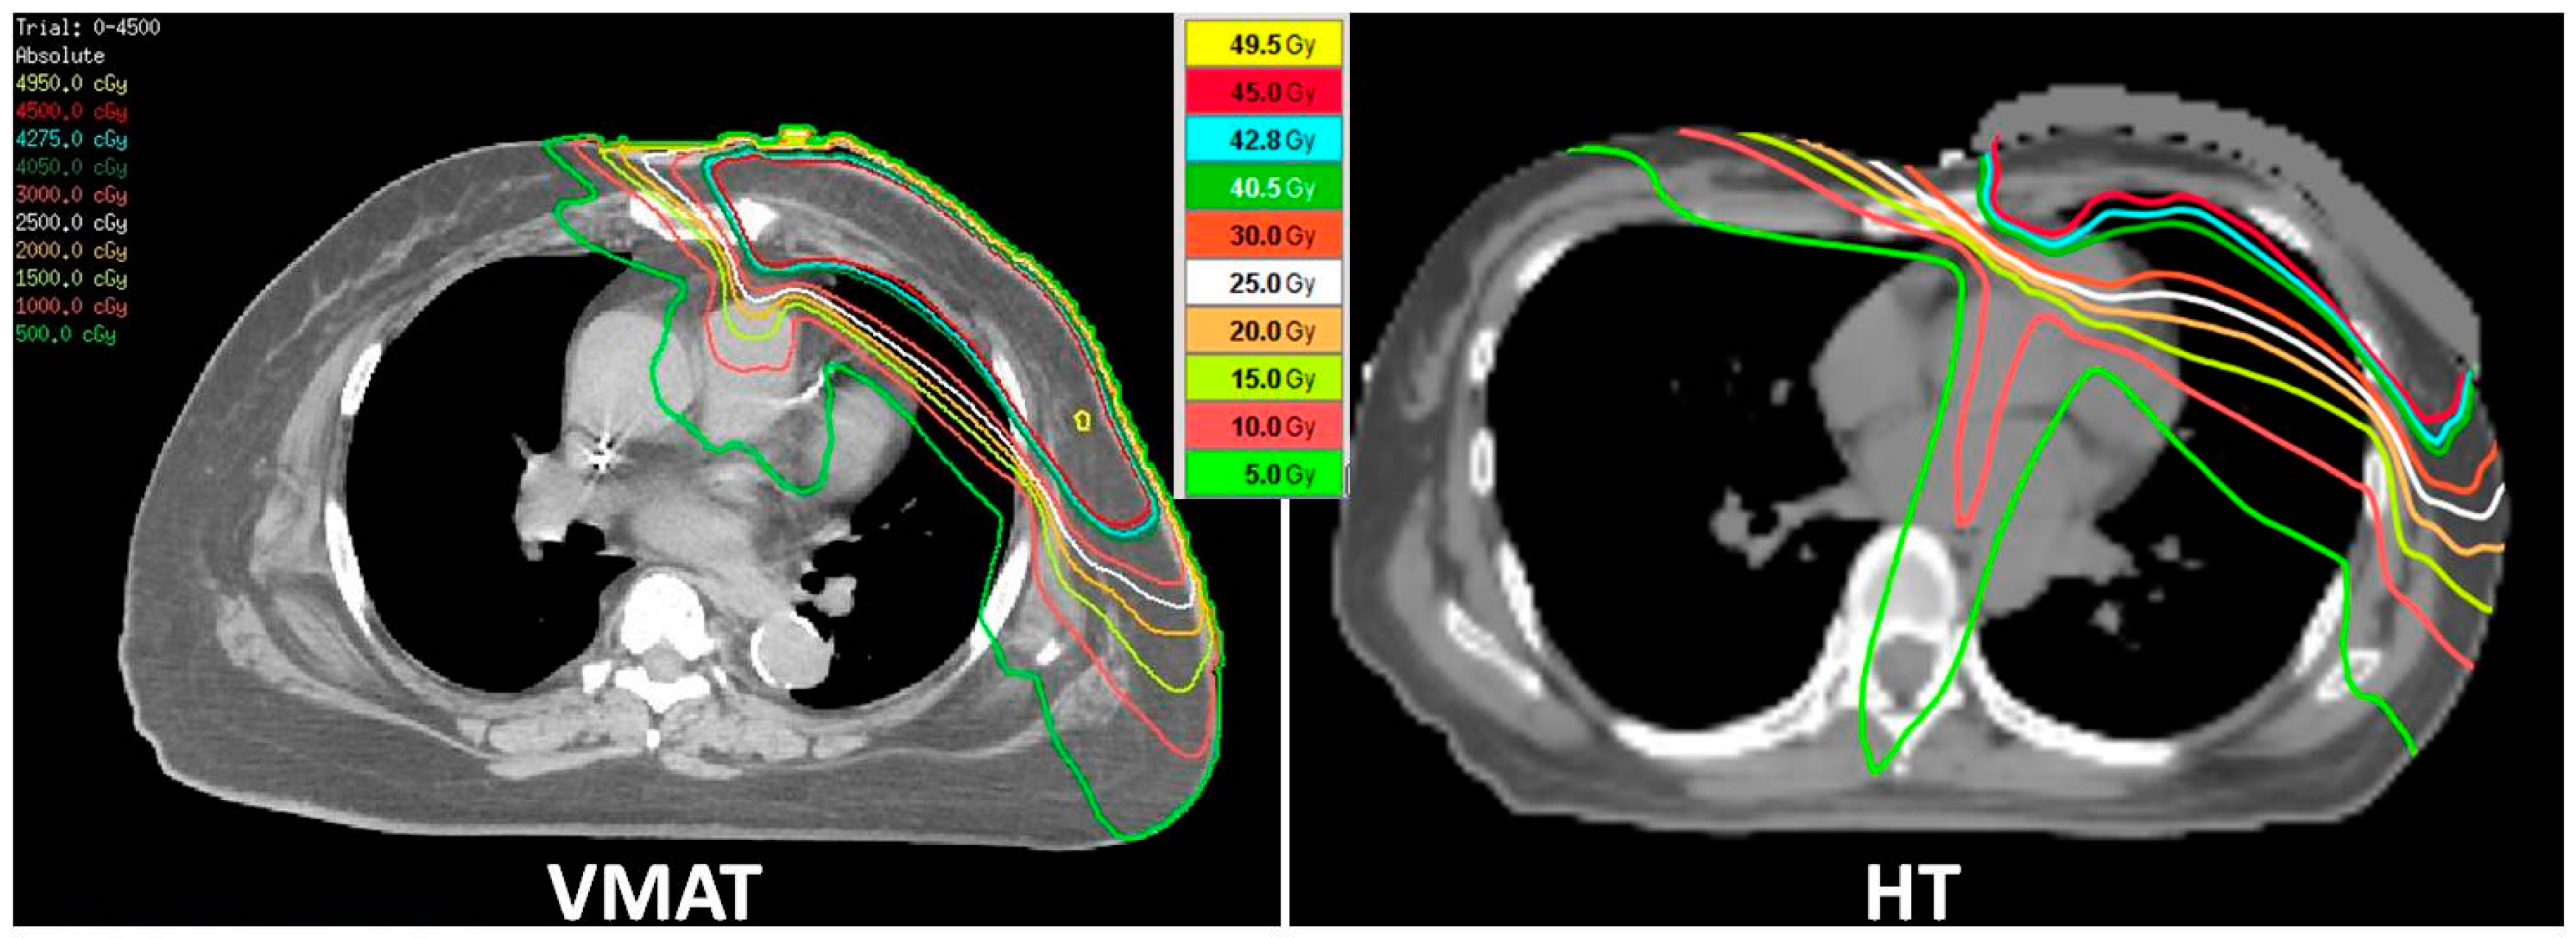

2.2. RT Treatment Plan

2.3. RT Technique and Dosimetric Evaluation